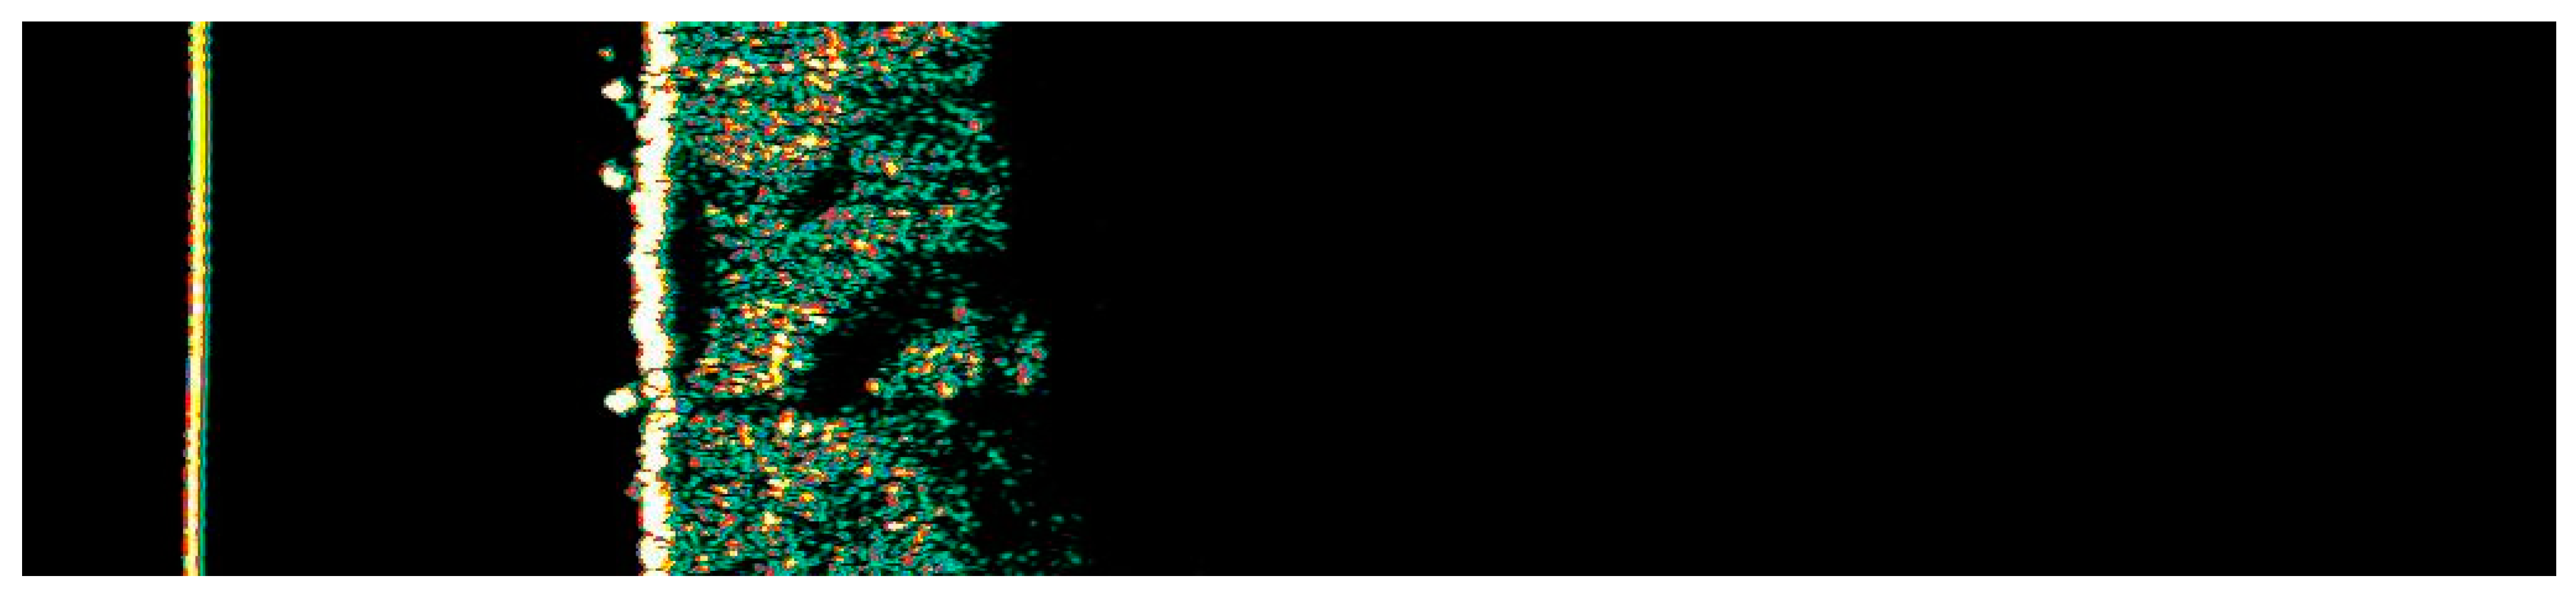

3.1. Clinical and Dermoscopic Involution of HIFU-Treated Basal Cell Carcinoma

| Number of Changes | Vascular Patterns | Pigment Structures | Non-Pigmented Structures | ||||||||||||||||

|---|---|---|---|---|---|---|---|---|---|---|---|---|---|---|---|---|---|---|---|

| Ambrozing Linear | Short Linear | Loop-like Linear | Bent Linear | Clod-like Linear | Radially Arranged | Segmentally Arranged | Reticular | Segmentally Arranged Linear | Radially Arranged Linear | Angular Linear | Small Gray-Blue Globules | Large Gray-Blue Globules | White Lines | Small White Structureless Areas | Pink Structureless Areas | White-Yellow Globules | Orange Globule–Crust | Rosettes | |

| 1. | X | 3 | X | ||||||||||||||||

| 2. | X | X | X | X | X | 2 | |||||||||||||

| 3. | X | X | X | ||||||||||||||||

| 4. | X | X | X | 2 | X | ||||||||||||||

| 5. | X | X | X | 3 | X | X | |||||||||||||

| 6. | X | X | X | X | X | 3 | X | ||||||||||||

| 7. | X | X | X | X | 3 | X | |||||||||||||

| 8. | X | X | X | X | 3 | ||||||||||||||

| 9. | X | X | X | 2 | |||||||||||||||

| 10. | X | X | X | 2 | X | ||||||||||||||

| 11. | X | X | 2 | X | |||||||||||||||

| 12. | X | X | 3 | X | |||||||||||||||

| 13. | X | X | X | X | X | ||||||||||||||

| 14. | X | 2 | X | ||||||||||||||||

| 15. | X | X | 3 | X | |||||||||||||||